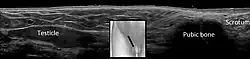

In the minority of cases with bilaterally nonpalpable testes, further testing to locate the testes, assess their function, and exclude additional problems is often useful. Scrotal ultrasound or magnetic resonance imaging performed and interpreted by a radiologist can often locate the testes while confirming the absence of a uterus. At ultrasound, the undescended testis usually appears small, less echogenic than the contralateral normal testis and usually located in the inguinal region. With color Doppler ultrasonography, the vascularity of the undescended testis is poor.